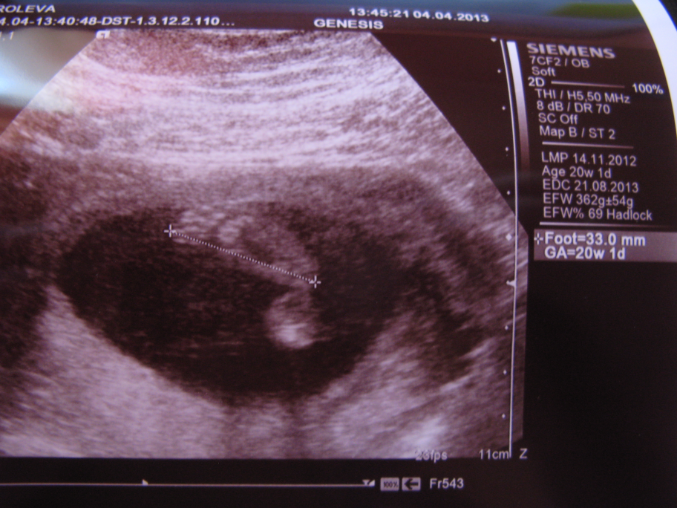

Наш экватор мы провели в Питере у родителей, поэтому отчет пишу чуть попозже:) Там же в питере съездили на 4D УЗИ:) остались очень довольны клиникой и врачами. Правда 4D почти нам не показали, малыш прятался так что сделали 2D и несколько раз включали 4D, но на диск записывать не стали, скромный у нас мальчик:)Доктор все подробно показала и рассказала, подробно осмотрели сердечко и мозг. Сказали что все у нас отлично! Малыш будет крупный:) на момент УЗИ нам было 20нед. 1дн., вес 362 гр. обхват головы - 182 мм, обхват животика - 150 мм., частота сердцебиения 146 уд. Отклонений не выявлено, вод в норма, вот только поставили что плацента низковато, но сказали вроде ничего страшного, я пока не читала по этому поводу ничего.

Это наша попа и ножка:) большего родителям решили не показывать:)

Это наши замечательные пяточки, бегающие по монитору, доктор только датчиком поймает а они топ топ по экрану, это было очень забавно

А это наша головушка вернее затылок:)